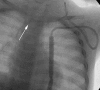

Central venous access is increasingly becoming the domain of the radiologist, both in terms of the insertion of central venous catheters (CVCs) and in the subsequent management of these lines. This article seeks to provide an overview of the CVC types available for paediatric patients and a more detailed explanation of the spectrum of complications that may lead to catheter malfunction. A standard catheter contrast study or 'linogram' technique is described. The normal appearances of such a study and a detailed pictorial review of abnormal catheter studies are provided, together with a brief overview of how information from catheter investigations can guide the management of catheter complications.